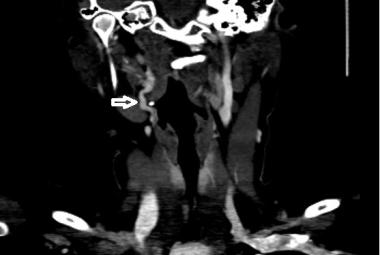

CTA showing tortuosity of right extracranial ICA at level C2 (white arrow)

Unilateral Pulsatile Tinnitus in Young Female Adults: A Report of Two Cases